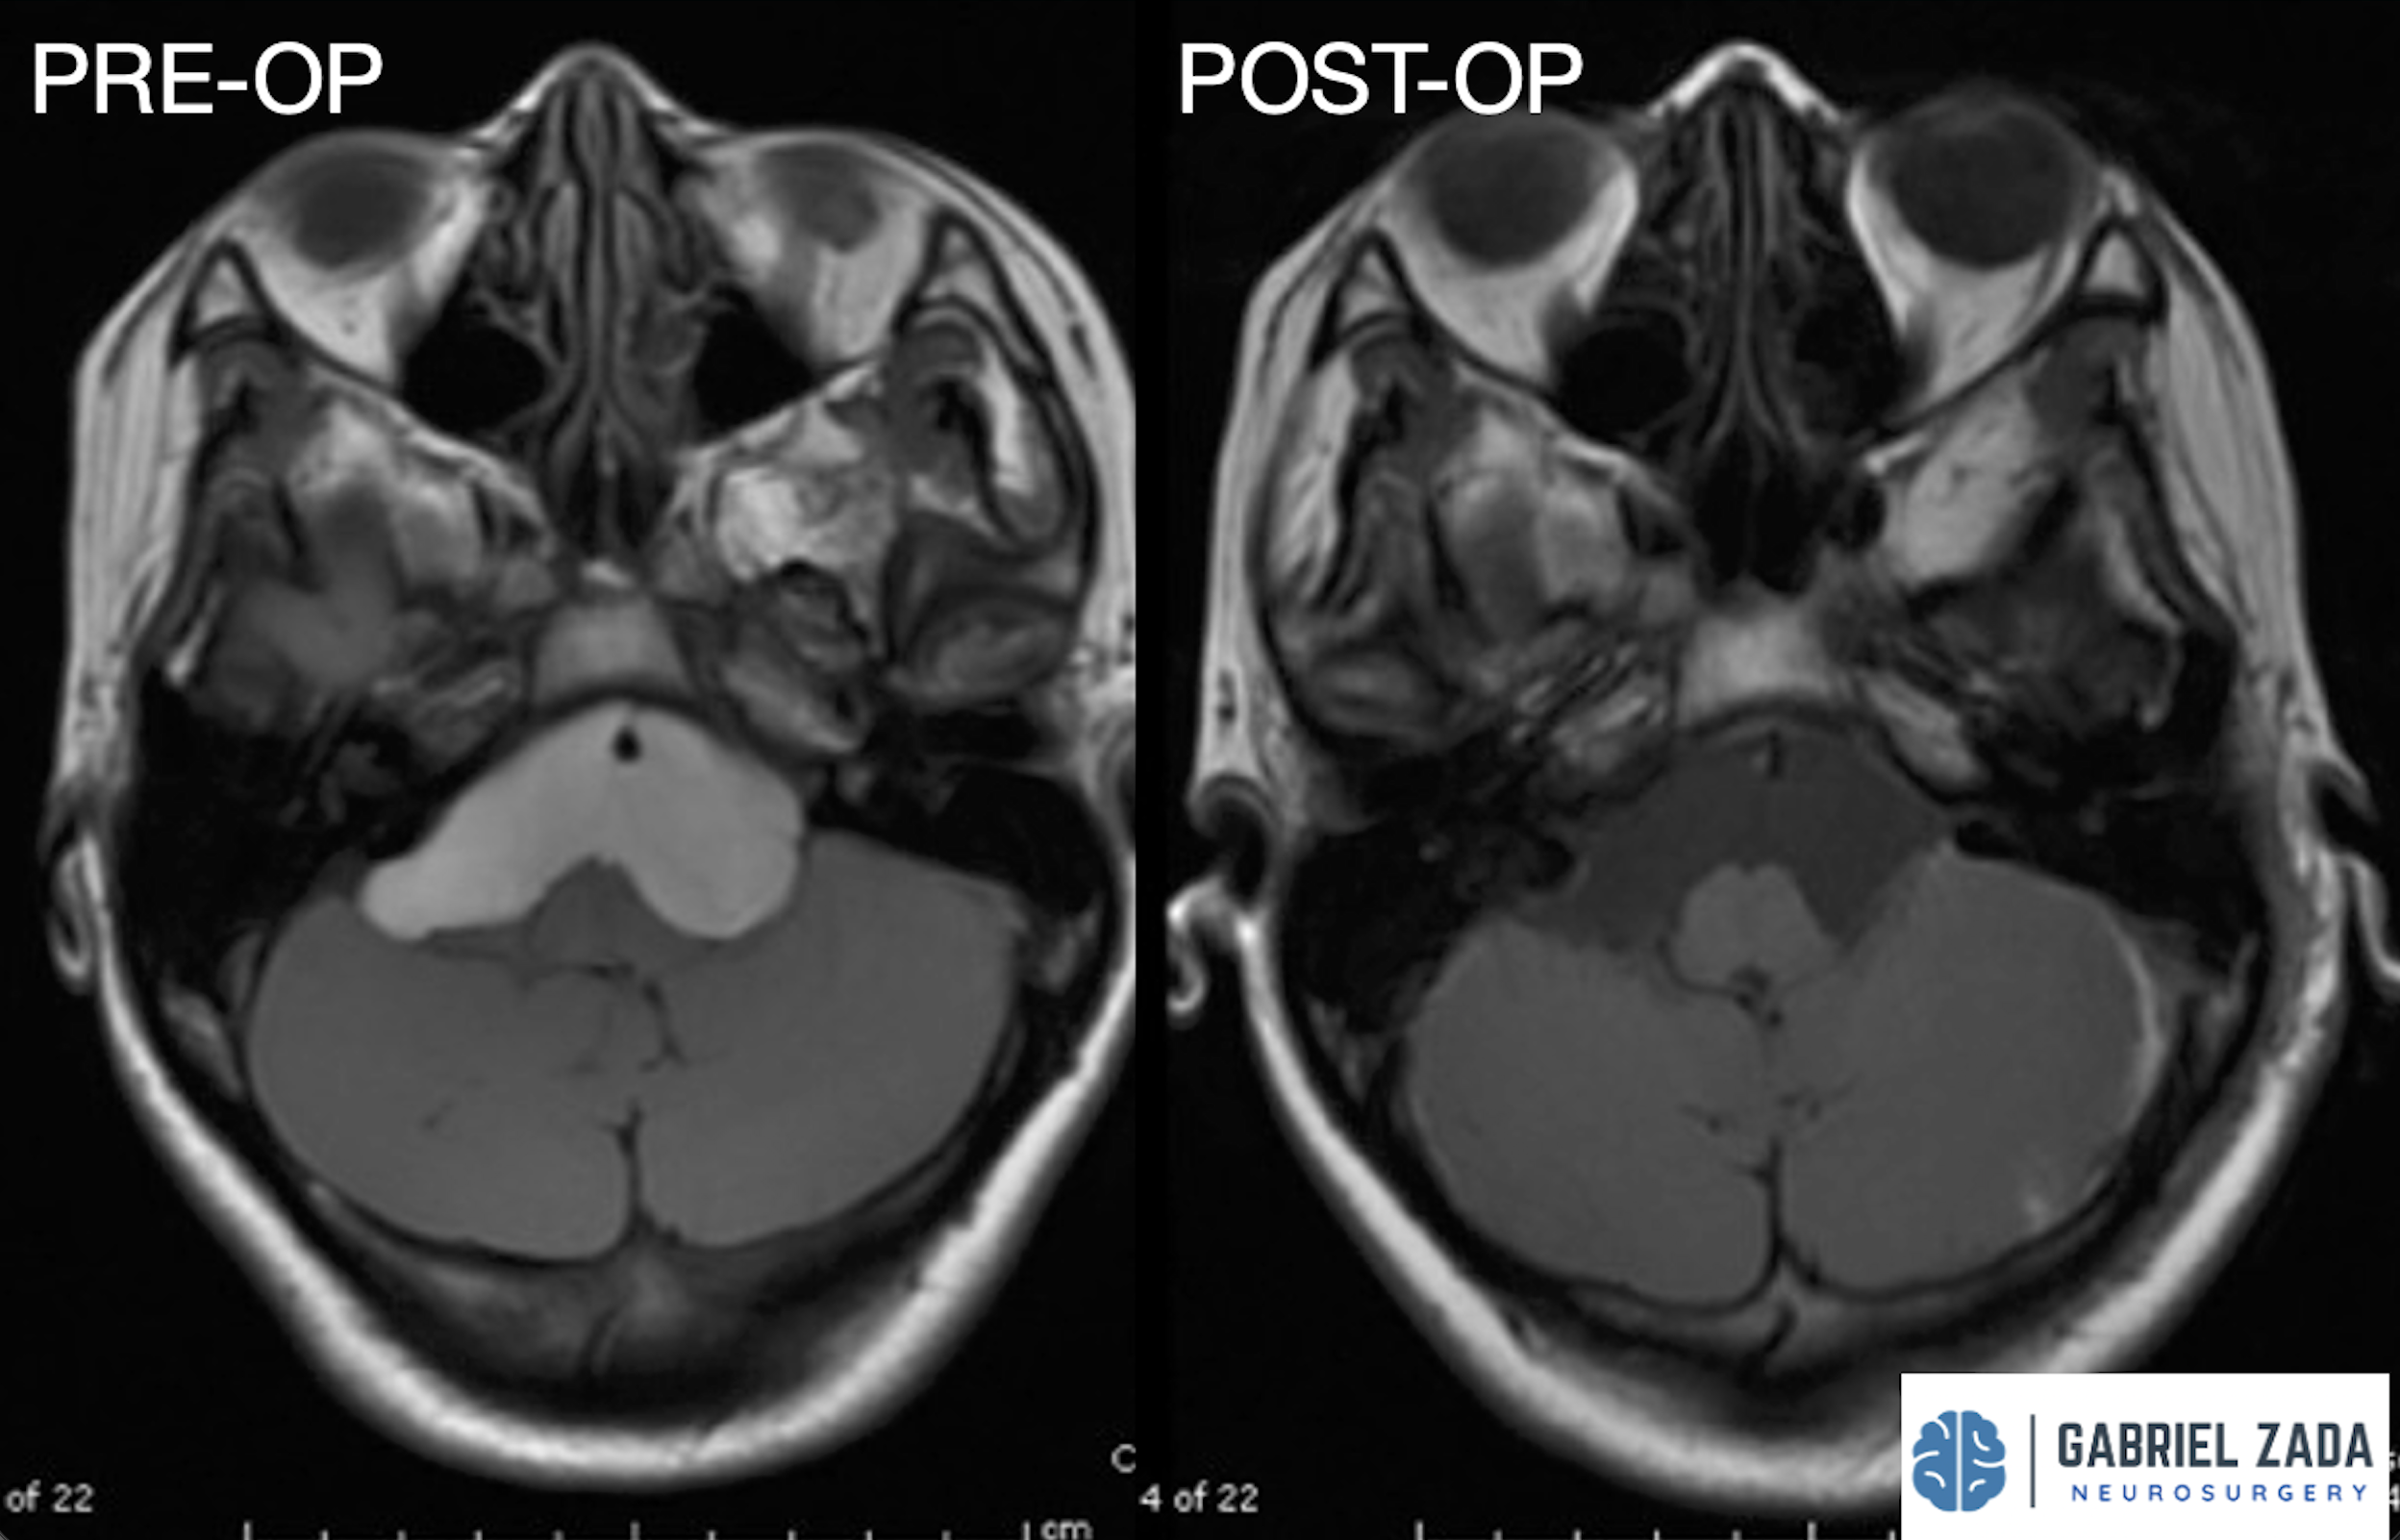

Explore this comprehensive gallery featuring pre‑ and post‑operative imaging of patients with skull‑base tumors treated by Gabriel Zada, MD, MS, FAANS, FACS. These cases highlight Dr. Zada’s expertise in advanced neurosurgical techniques and outcomes.

*Representative cases shown for educational purposes. All images de-identified. Individual results vary.